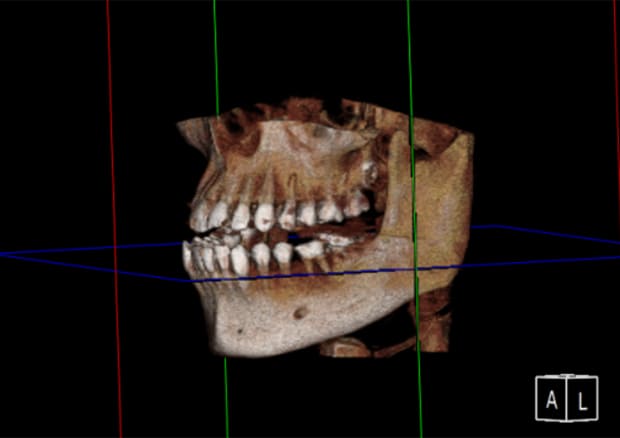

CTスキャンによる診断

すべての歯科治療において診査診断は非常に重要です。

CTスキャンによる検査をすることで歯根の状態をしっかり把握し治療計画を立てることができます。

診査診断をしっかりすることで治療の質の向上につながります。